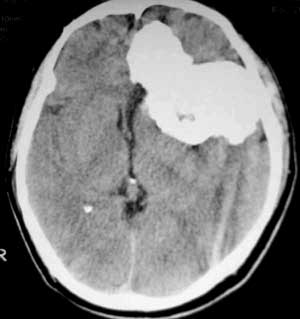

男性,60岁,反复癜痫40余年。

病理结果

:

骨软骨瘤